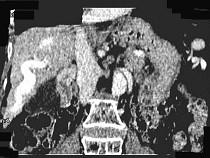

问题 女,70岁,发现乙型肝炎10年,3年前CT诊断为肝硬化,CT检查见图,最可能的诊断是 ( )

选项 A.肝癌 B.肝硬化、肝血管瘤 C.肝硬化、门脉瘤样扩张 D.肝门脉畸形 E.肝转移瘤、门脉扩张

答案 C